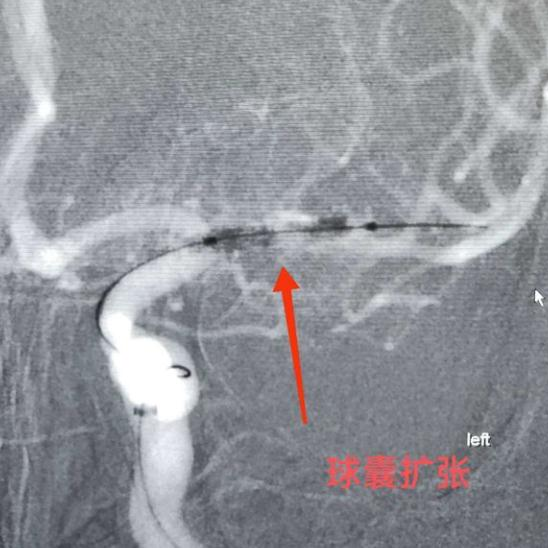

球囊扩张狭窄段